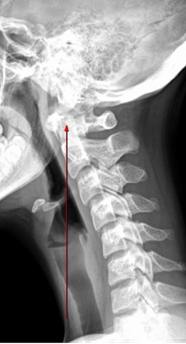

How does neck alignment influence whole-body posture?

Cervical curve position sets head balance; loss of lordosis shifts loads forward, overworking muscles and distorting alignment down the chain.

The neck is often the lead actor in the posture conversation, especially with how common the phrase “tech neck” has become. In fact, kids and teens are showing signs of tech neck (also known as “text neck”) earlier as screen time continues to rise.

But there’s more to the story. The neck is actually the fifth floor of a compensatory building. After performing thousands of Structural Fingerprint® Exams (including x-rays), I can tell you everyone shows some mix of imbalances in the feet, knees, femoral head heights, and lumbar spine. The neck will only position itself in a way that provides balance to the entire structure.

Add to this the fact that fewer than 10% of people have a normal cervical curve with a normal cervical gravity line (Fig. 2), and good posture becomes an even greater challenge. Most people develop varying degrees of abnormal curves and abnormal gravity lines (Fig. 3) long before they ever buy their first smartphone.

Obviously, when you look at the Key Characteristics of Good Posture, “ears aligned over the shoulders” is much harder for someone in Fig. 3 than in Fig. 2, yet we still expect the same result: “Sit up straight.” But every person’s structure is 100%unique, asymmetrical, and imbalanced. Wouldn’t it make more sense to understand those differences and see the findings for each individual? And wouldn’t it be smart for the chiropractic profession to lead the way in valuing posture and promoting detailed testing that allows for custom recommendations for everyone?